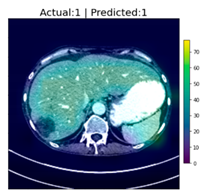

| 1 | ![]() | Has Tumor | Has Tumor | Has Tumor | Some |

| 2 | ![]() | Has Tumor | Has Tumor | Has Tumor | Yes |

| 3 | ![]() | Has Tumor | Has Tumor | Has Tumor | Yes |

| 4 | ![]() | Has Tumor | Has Tumor | Has Tumor | Yes |

| 5 | ![]() | Has Tumor | Has Tumor | Has Tumor | Yes |

| 6 | ![]() | No Tumor | Has Tumor | Has Tumor | Yes |

| 7 | ![]() | Has Tumor | Has Tumor | Has Tumor | Yes |

| 8 | ![]() | Has Tumor | Has Tumor | Has Tumor | Yes |

| 9 | ![]() | Has Tumor | Has Tumor | Has Tumor | Some |

| 10 | ![]() | Has Tumor | Has Tumor | Has Tumor | Yes |

| 11 | ![]() | Has Tumor | Has Tumor | No Tumor (Cyst) | Some |

| 12 | ![]() | Has Tumor | Has Tumor | Has Tumor | Yes |

| 13 | ![]() | Has Tumor | Has Tumor | No Tumor | Yes |

| 14 | ![]() | Has Tumor | Has Tumor | No Tumor (Inflammation of the Biliary Tract) | Some |

| 15 | ![]() | No Tumor | Has Tumor | No Tumor (Cyst) | Some |

| 16 | ![]() | Has Tumor | Has Tumor | Has Tumor | Yes |